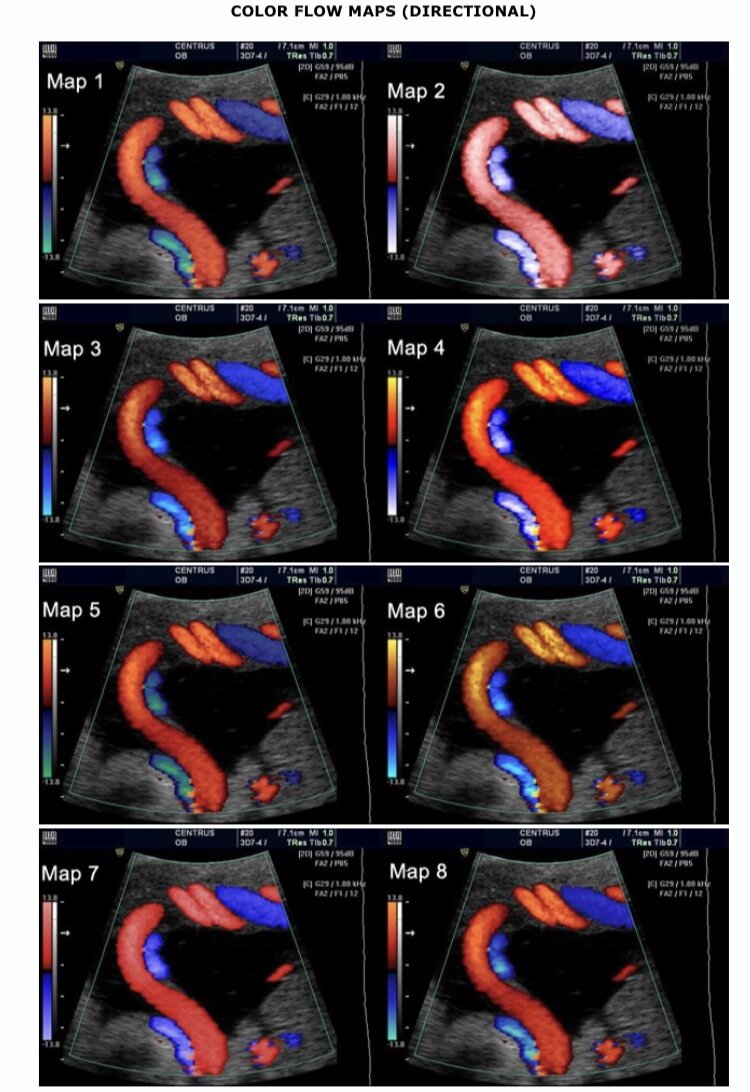

Фото с сайта FMF.org , на фотографии изображены сосуды плаценты.

Также, при проведении ультразвукового исследования на 1 скрининге проводится допплерометрия маточных артерий. Обязательным критерием успешного проведения допплерометрии считается использование пульсационного индекса (ПИ). Если средние значения ПИ будут выходить за пределы 95й процентили, то беременные будут включены в группу высокого риска. Также необходимо помниты, что одностороннее увеличение ПИ считается неинформативным, только среднее значение при обязательном исследовании маточных артерий с обеих сторон.